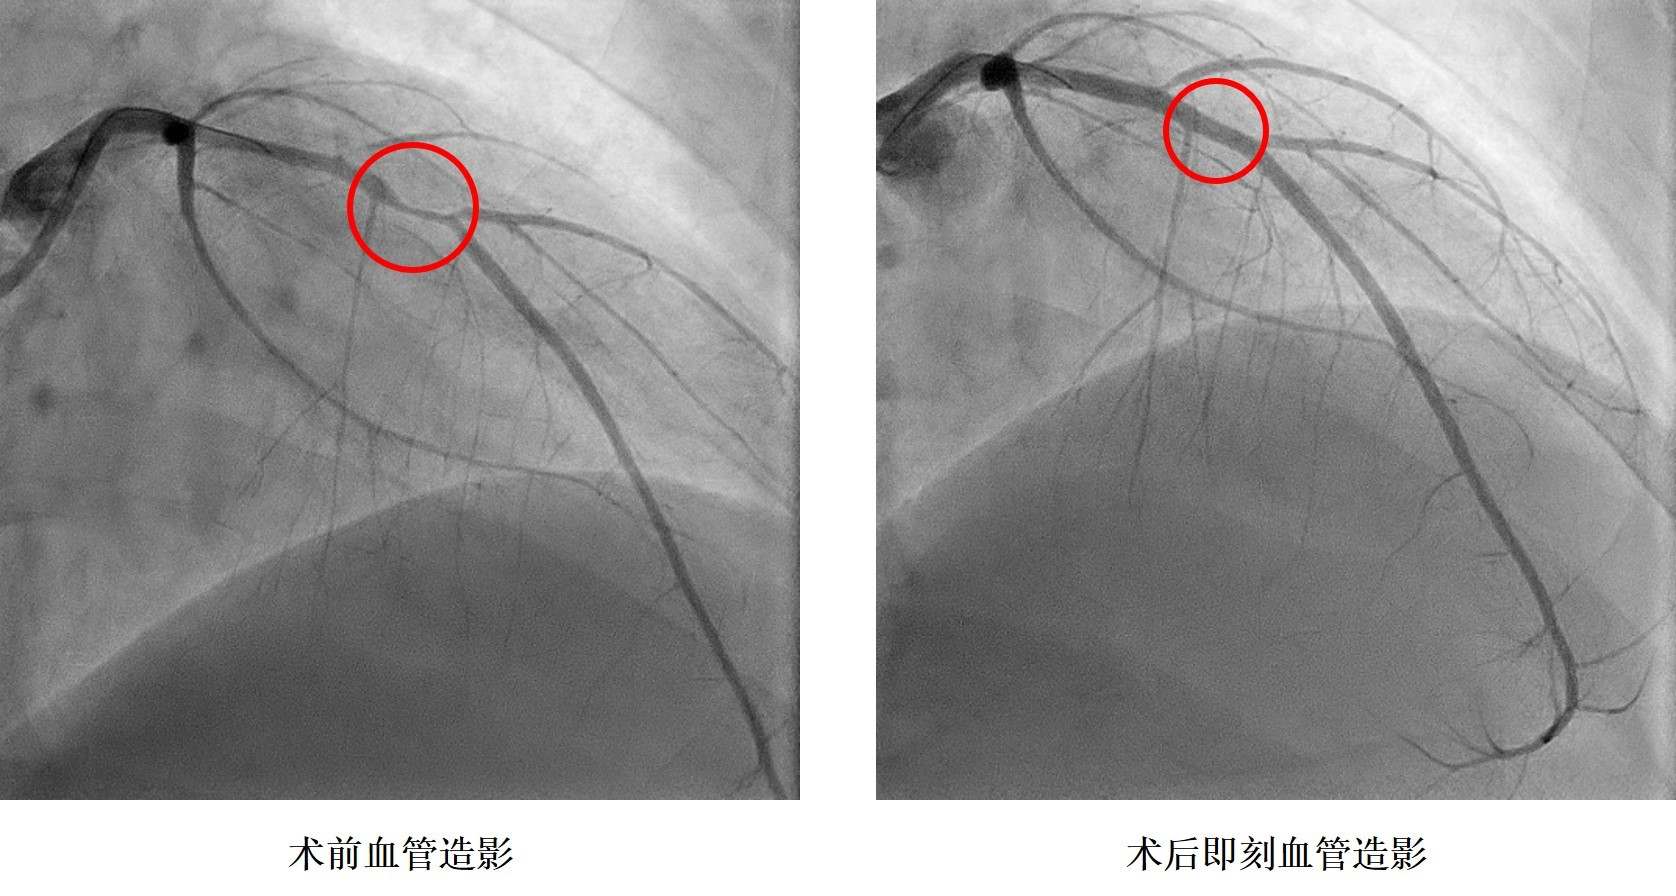

小浩在2019年9月6日晚飯時突感胸痛、胸口悶、呼吸困難,立即前往湖南省人民醫(yī)院胸痛中心就診,診斷為急性心肌梗死,小浩被送往介入手術(shù)室,進行急診造影后發(fā)現(xiàn)冠狀動脈血管嚴(yán)重狹窄,需要在體內(nèi)植入心臟支架。據(jù)了解小浩從14歲就開始了抽煙,還發(fā)現(xiàn)了高血壓,血壓最高200mmHg,卻一直沒有規(guī)律服藥治療。16歲讀完技校后的他開始過上了淘寶電商的生活,生活日夜顛倒,夜間修圖、改片,并頓頓燒烤,白天睡覺,缺乏運動,這樣的生活維持了兩年本次。入院后同時發(fā)現(xiàn)了糖尿病,這一系列原因是導(dǎo)致小浩發(fā)生心肌梗死的罪魁禍?zhǔn)住?/p>

孩子還這么小,人生剛剛開始就要帶上心臟支架生活嗎?心內(nèi)科鄭昭芬主任組織團隊進行了會診,建議植入生物可吸收心臟支架!拔覀儽緛聿辉敢庵踩胄呐K支架,但聽說有一種新型的心臟支架在植入體內(nèi)后幾年就能降解,就接受了!痹谡鞯眯『票救撕图胰送夂,心內(nèi)三科潘宏偉主任利用血管內(nèi)超聲指導(dǎo),順利植入生物可吸收心臟支架,拆除了小浩體內(nèi)的“炸彈”。